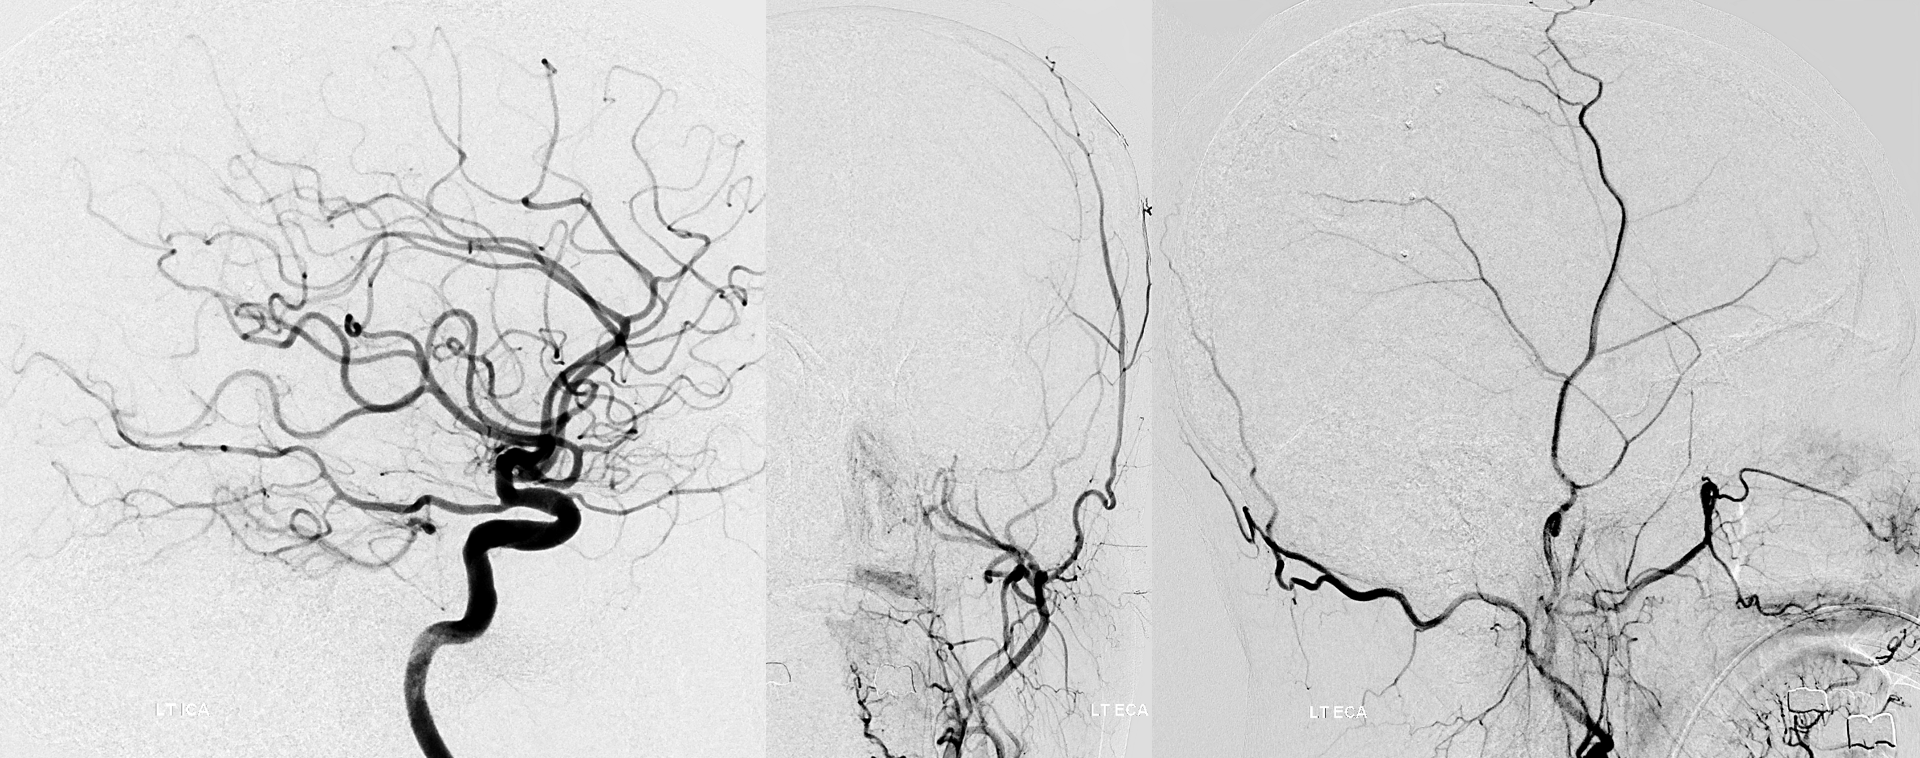

Chronic cortical ischemia promotes natural recruitment of meningeal vessels to help supply the brain, known as autosynangiosis, in contrast to the surgical synangiosis which aims to accomplish the same purpose by overlaying dura, muscle, drilling holes, etc in the head.  This process is more robust in younger patients, often encountered in angiographic evaluation of Moya Moya disease. Here is an example in a 4 year old with Moya Moya with severe ACA territory disease, and secondary MMA autosynangiosis helping out this territory.

ECA, MMA authsynagniosis

Notice also a faint autosynangiosis between ethmoid arteries from the ophthalmic and frontal lobe base.